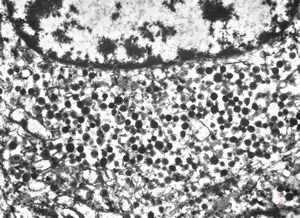

M,66y. | siderosomes

M,66y. | hemosiderin - siderosomes